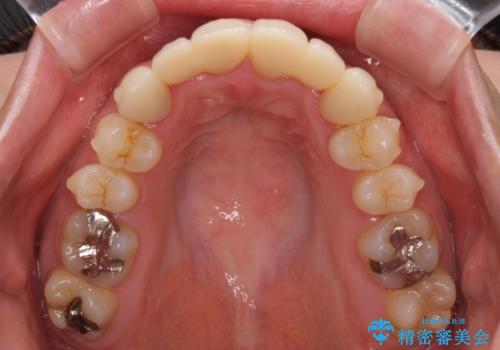

- 審美的ではない上の前歯とデコボコの下の前歯、歯茎が腫れている奥歯を気にして来院された患者様です。

根管治療の必要な歯がいくつかあるため、まずは根管治療を行い、その後インビザラインにて矯正治療を行うこととしました。

矯正治療後に前歯をセラミックブリッジに、奥の銀歯はセラミックインレーやPGAインレー(ゴールドインレー)にて補綴・修復治療を行うこととしました。